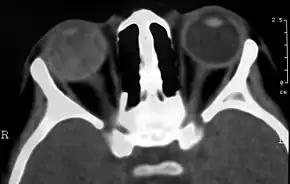

Medical imaging

Imaging studies such as ultrasonography (US), Computerized Tomography (CT) and Magnetic Resonance Imaging (MRI) can aid diagnosis. On ultrasound, Coats' disease appears as a hyperechoic mass in the posterior vitreous without posterior acoustic shadowing; vitreous and subretinal hemorrhage may often be observed.[7][8]

On CT, the globe appears hyperdense compared to normal vitreous due to the proteinaceous exudate, which may obliterate the vitreous space in advanced disease. The anterior margin of the subretinal exudate enhances with contrast. Since the retina is fixed posteriorly at the optic disc, this enhancement has a V-shaped configuration.[2]